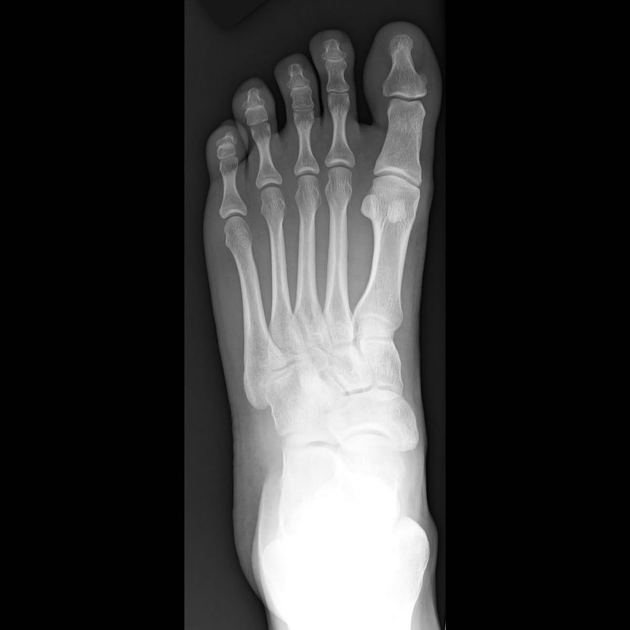

통풍 진단은 다양한 검사 방법이 사용됩니다. 임상적으로 가장 중요한 것은 혈액 검사를 통해 혈중 요산 수치를 확인하는 것입니다. 요산 수치가 6.8mg/dL 이상인 경우 통풍으로 의심하게 됩니다. 또한, 관절에서 체액을 채취하여 요산 결정체의 존재 여부를 확인하는 관절천자도 시행될 수 있습니다. X-ray와 MRI와 같은 영상 검사는 관절 손상의 정도를 평가하는 데 도움을 줄 수 있습니다. 정확한 진단을 위해 의료 전문의와 상담하는 것이 중요합니다.